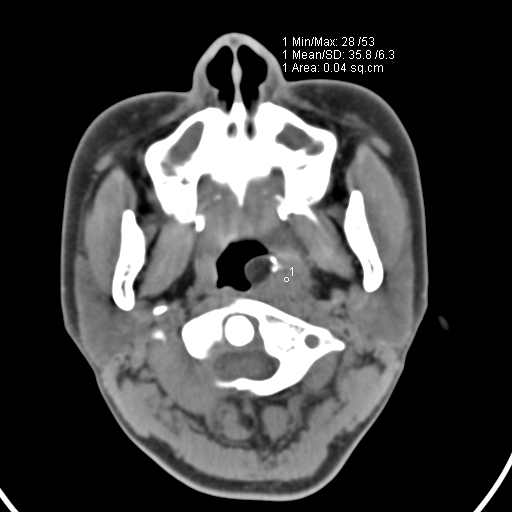

以下是引用zjzjr在2008-12-5 11:46:00的发言:[br]脂肪密度,壁有钙化.考虑口咽部皮样囊肿可能性大.双侧上颌窦炎,双侧下鼻甲粘膜肥厚.增殖腺肥大,扁桃体亦增大,考虑炎性.

以下是引用随光逐影在2008-12-5 18:27:00的发言:[br]1)考虑左侧茎突过长综合征并茎突舌骨韧带囊肿形成突入咽部;左侧咽部慢性炎症。2)鼻咽腺样体肥大。3)双侧扁桃体肿大。4)双侧上颌窦炎。5)双侧下鼻甲粘膜肥厚。